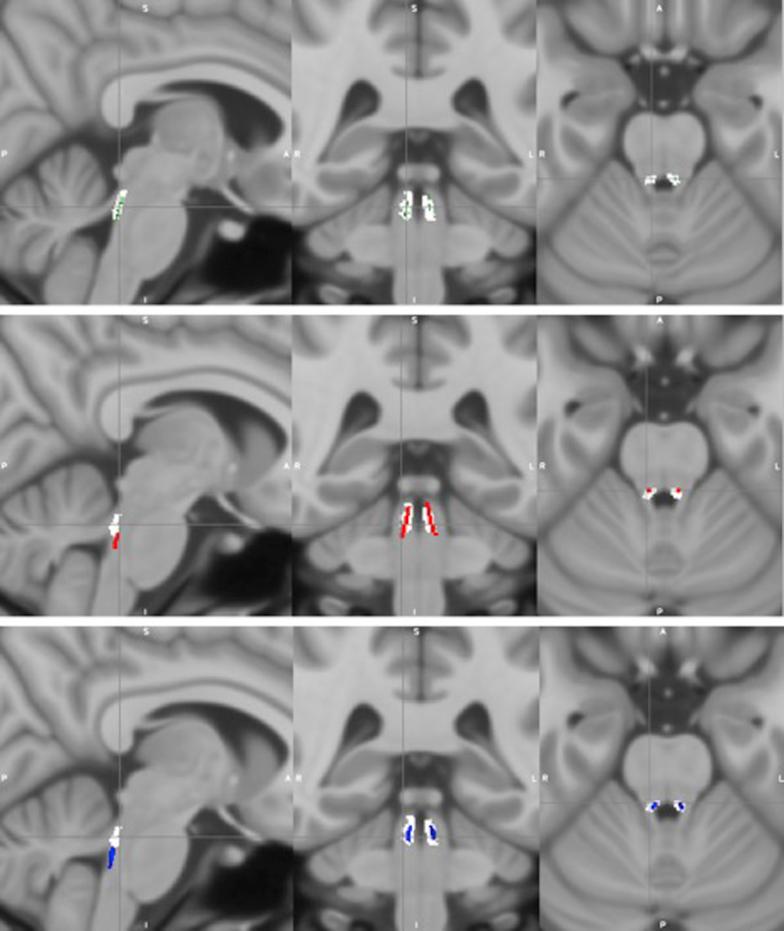

In vivo visualization of age-related differences in the locus coeruleus.

The locus coeruleus (LC), the major origin of noradrenergic modulation of the central nervous system, may play an important role in neuropsychiatric disorders including Parkinson's disease and Alzheimer's disease. The pattern of age-related change of the LC across the life span is unclear. We obtained normalized, mean LC signal intensity values, that is, contrast ratios (CRs), from magnetization transfer-weighted images to investigate the relationship between LC CR and age in cognitively normal healthy adults (N = 605, age range 18-88 years). Study participants were part of the Cambridge Centre for Ageing and Neuroscience-an open-access, population-based data set. We found a quadratic relationship between LC CR and age, the peak occurring around 60 years, with no differences between males and females. Subregional analyses revealed that age-related decline in LC CR was confined to the rostral portion of the LC. Older adults showed greater variance in overall LC CR than younger adults, and the functional and clinical implications of these observed age-related differences require further investigation. Visualization of the LC in this study may inform how future scanning parameters can be optimized, and provides insight into how LC integrity changes across the life span.